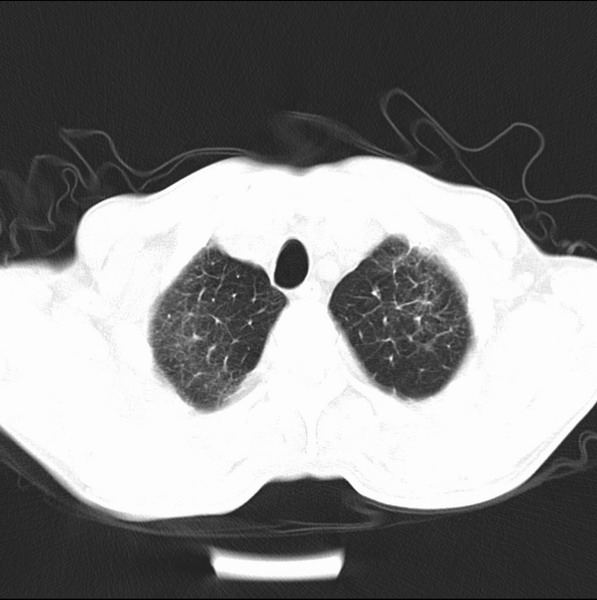

标题: CT19600:能否诊断为转移?

女、55

3年前盲肠癌、一年半前诊断膀胱癌,现在呼吸困难,临床考虑为肺转移

请问胸部ct如何诊断?能否排除淋巴管炎,纵隔窗没有问题。